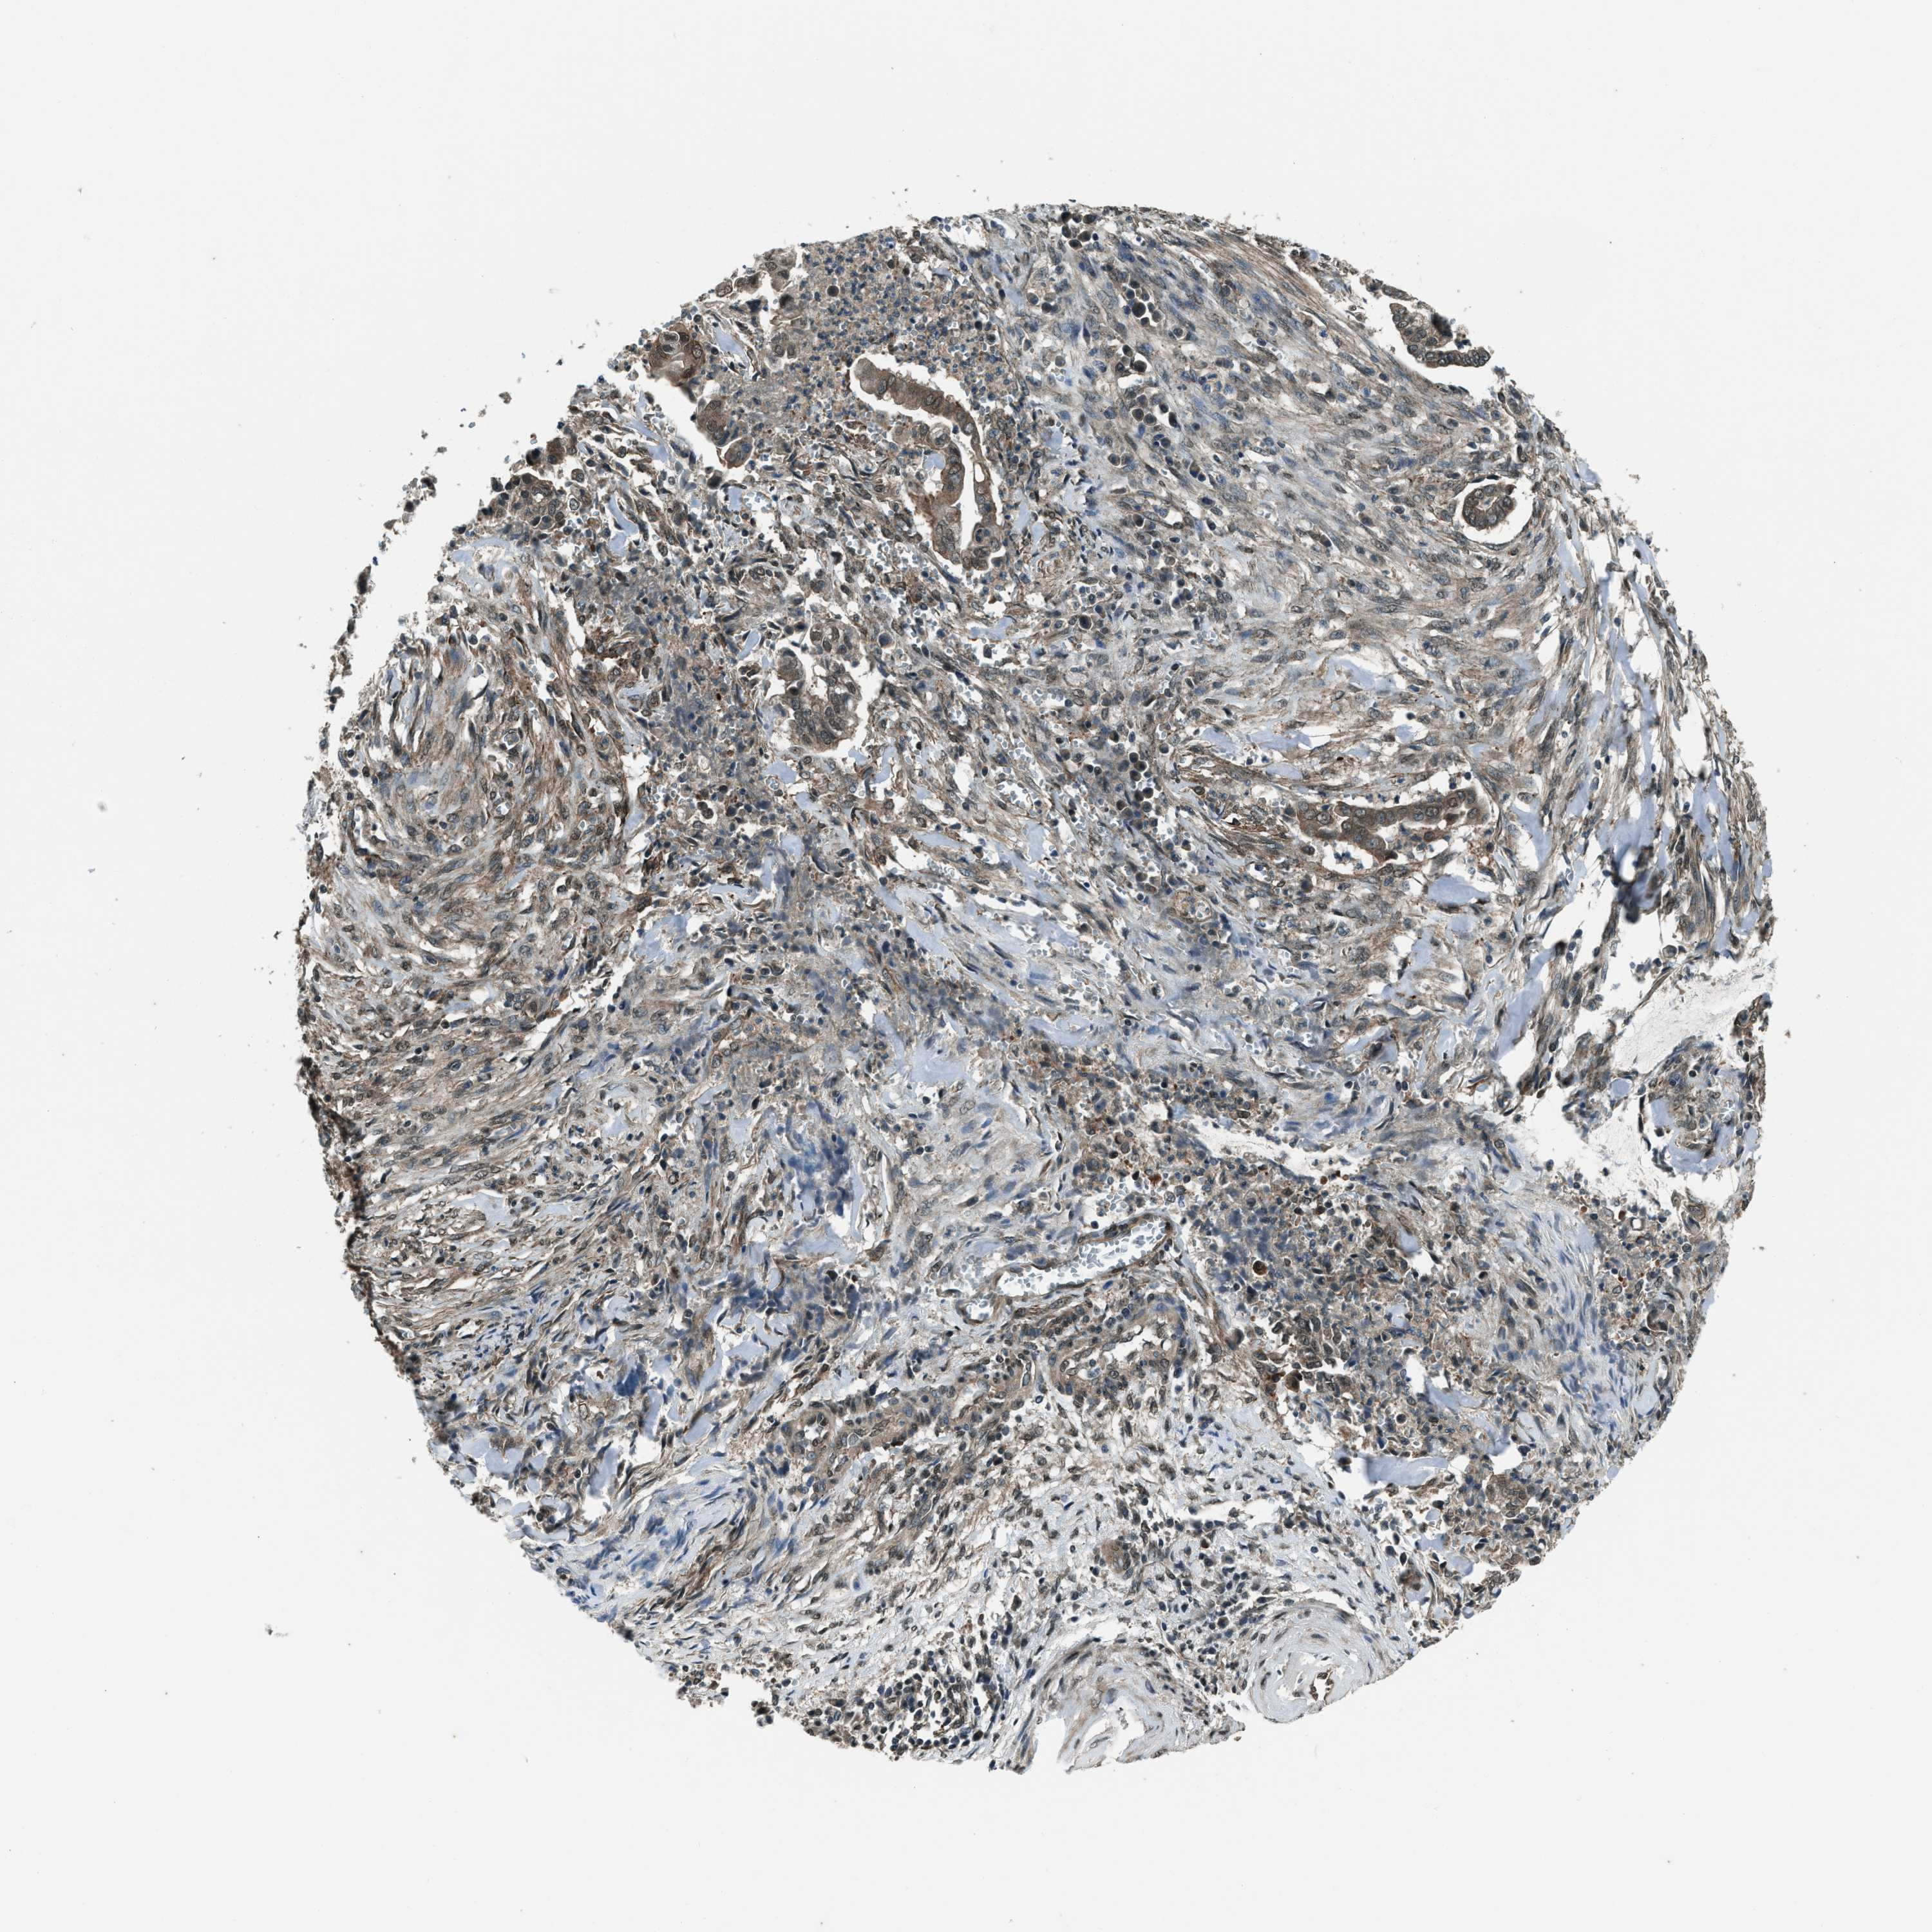

CERVICAL CANCER - Protein expressioni

A mouse-over function shows sample information and annotation data. Click on an image to view it in a full screen mode. Samples can be filtered based on level of antibody staining by selecting one or several of the following categories: high, medium, low and not detected. The assay and annotation is described here.

Note that samples used for immunohistochemistry by the Human Protein Atlas do not correspond to samples in the TCGA dataset.

Antibody stainingi

Antibody staining in the annotated cell types in the current human tissue is reported as not detected, low, medium, or high, based on conventional immunohistochemistry profiling in selected tissues. This score is based on the combination of the staining intensity and fraction of stained cells.

Each image is clickable and will lead to virtual microscopy that enables deeper exploration of all samples and also displays staining intensity scores, fraction scores and subcellular localization as well as patient and tissue information for each sample.

Antibody HPA020095

Antibody HPA020138

Antibody CAB010878

Antibody CAB080402

Squamous cell carcinoma, NOS

Adenocarcinoma, NOS